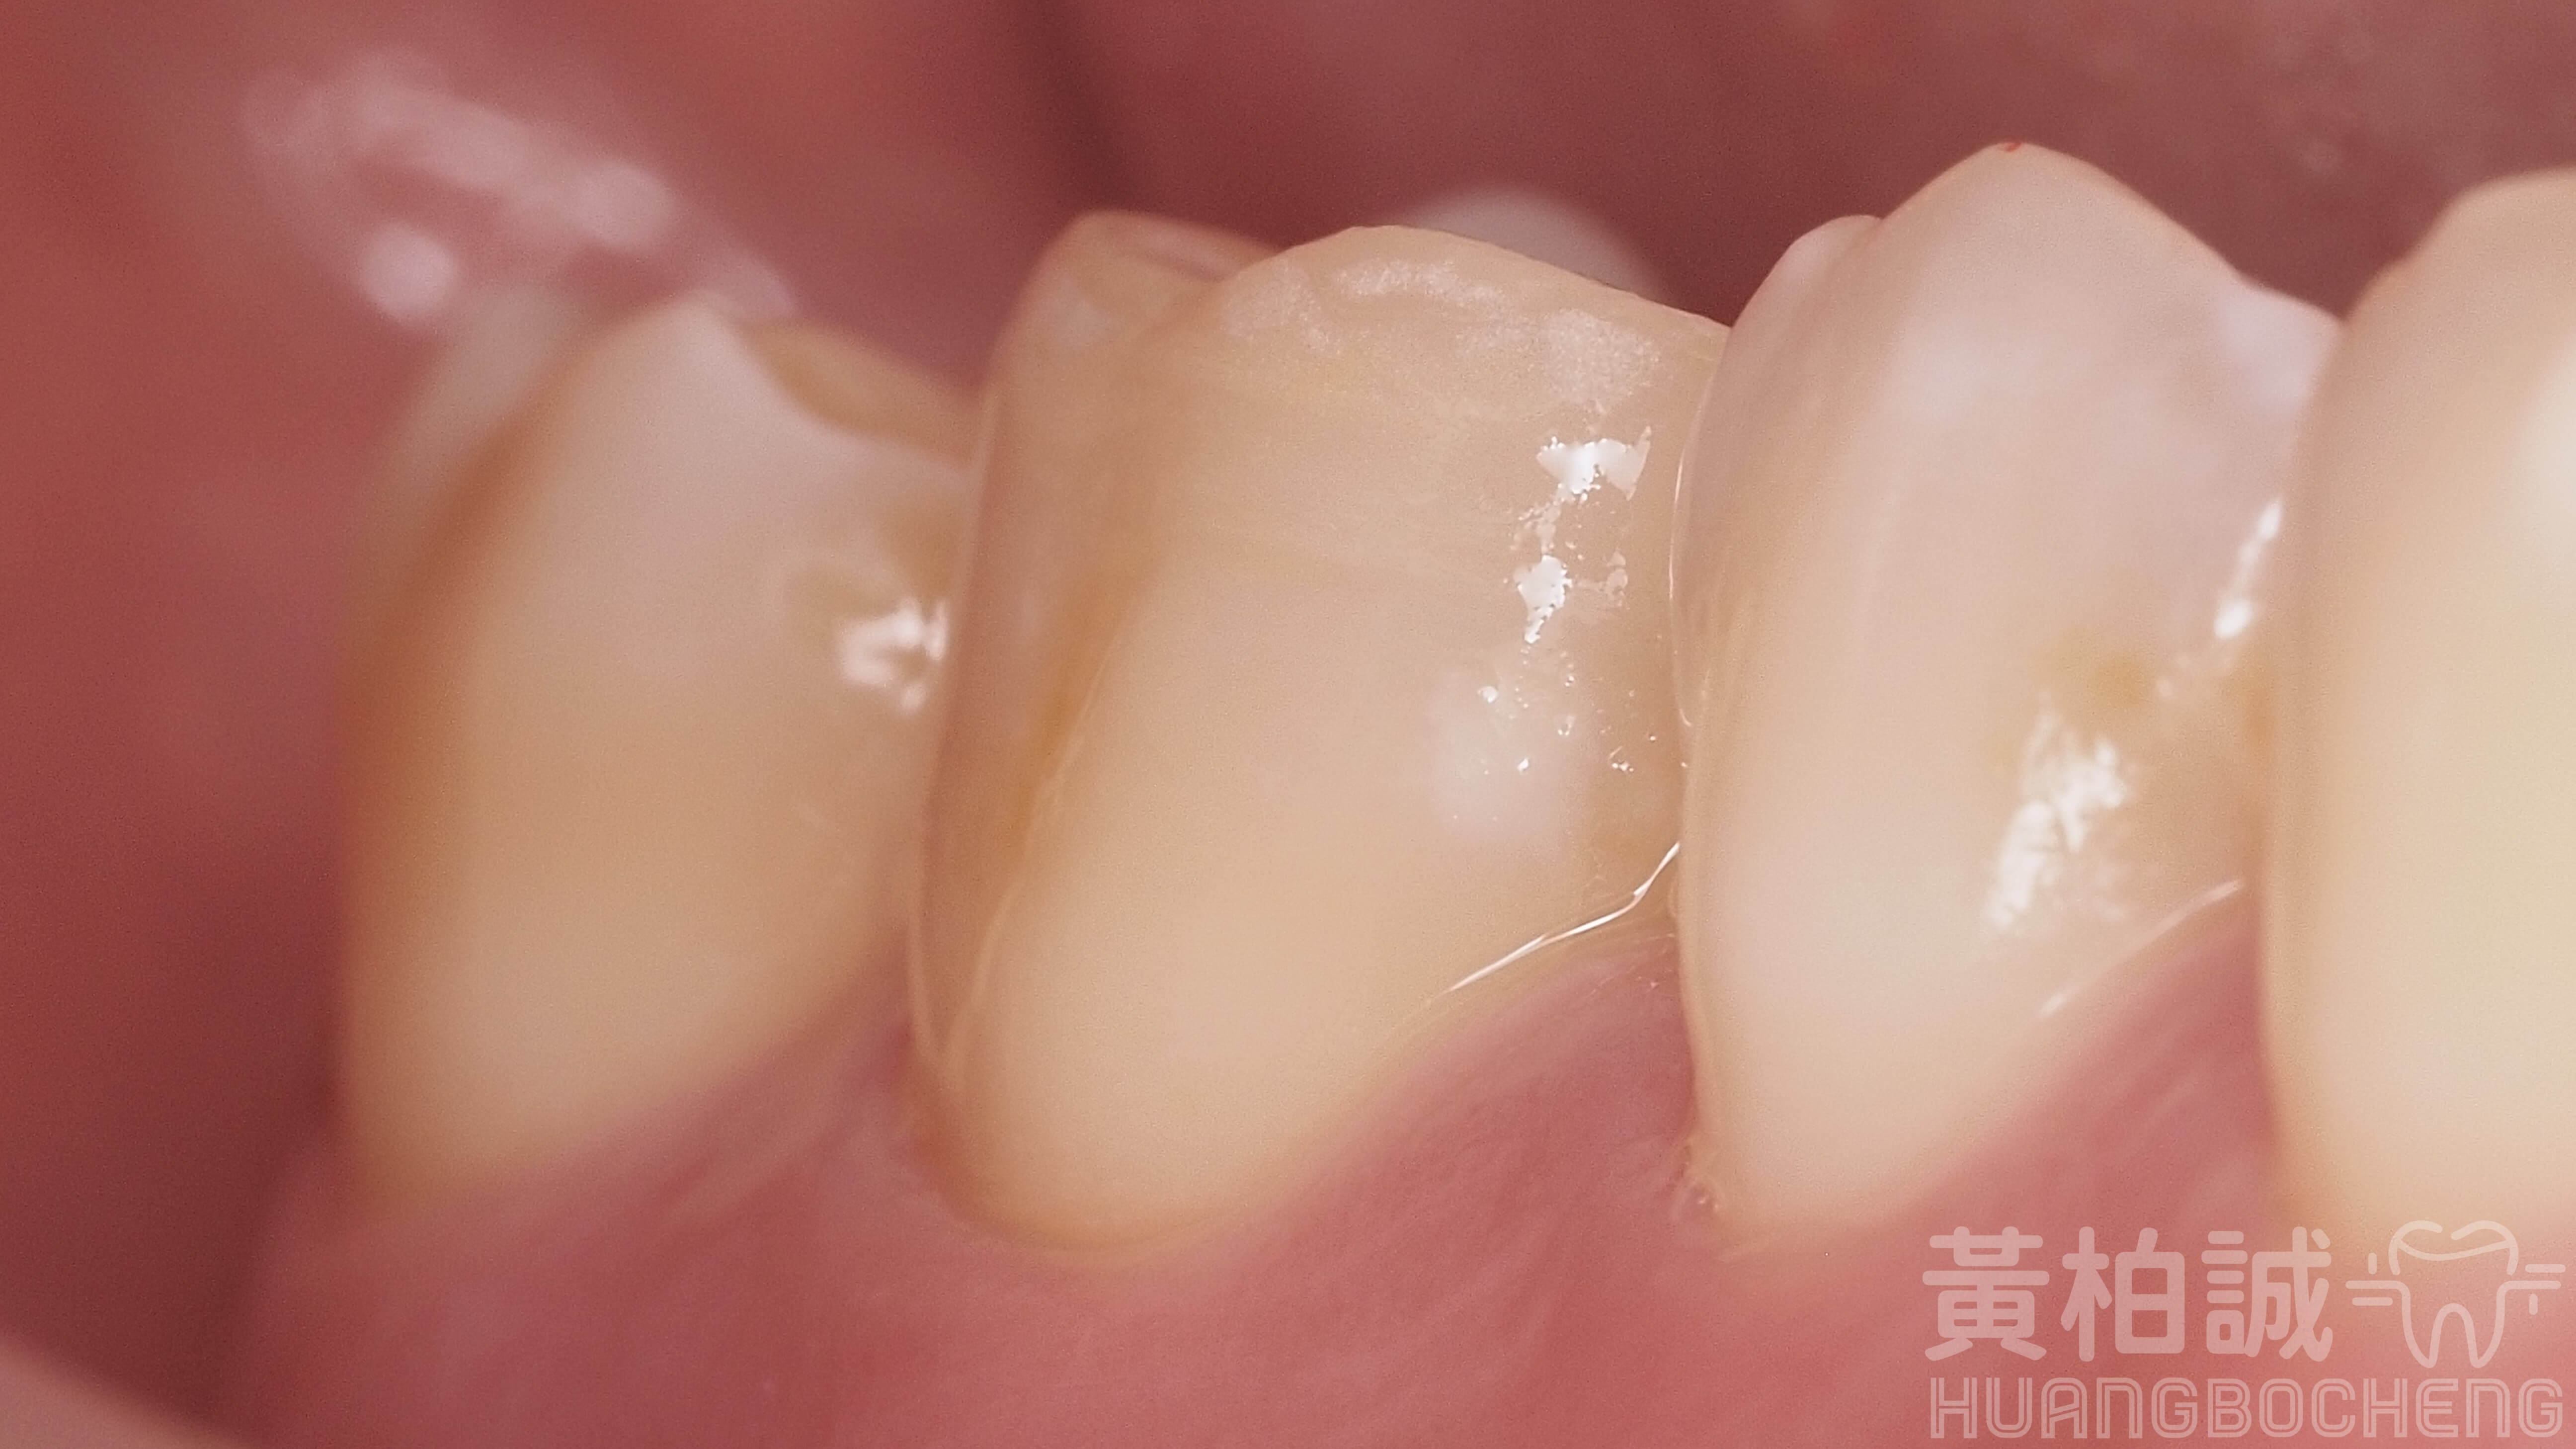

一個完美的3D齒雕應該要看起來與患者的牙齒會是嚴絲合縫的狀態,密合到幾乎看不出任何接隙存在的。

只有這樣嚴絲合縫的品質才能讓患者使用長長久久、不粗糙刮舌、並且大幅避免未來齒質再次崩壞的機率。